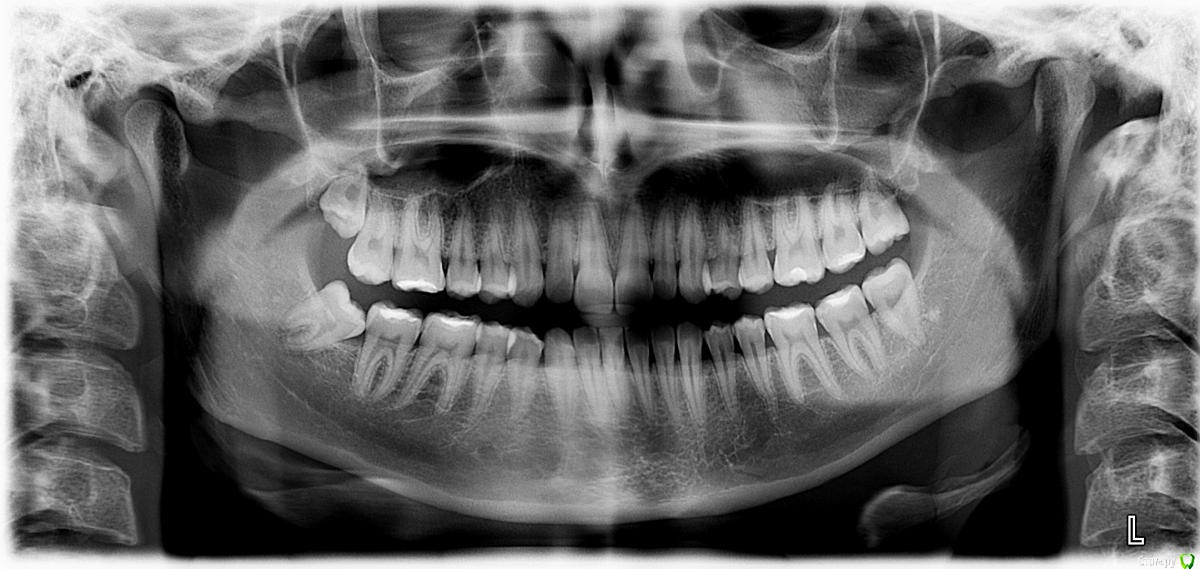

alyona_m Опубликовано 11 декабря, 2015 Поделиться Опубликовано 11 декабря, 2015 Здравствуйте!Врач отправил к хирургу на удаление 8-ки,но хирург рекомендовал подумать,т.к. воспаления нет,зуб по сути здоровый.Сейчас не болит,немного опухала и кровила десна,когда он рос (рос около 3 лет). Мне 24. Посоветуйте,пожалуйста,стоит удалять сейчас или оставить как есть? Ссылка на комментарий

diesel87 Опубликовано 11 декабря, 2015 Поделиться Опубликовано 11 декабря, 2015 Вы про правую нижнюю имеете в виду? Удаляйте планово, пока не заболело, он все равно на удаление уходит. Ссылка на комментарий

IvanK Опубликовано 11 декабря, 2015 Поделиться Опубликовано 11 декабря, 2015 Справа 8ки удалять 1 Ссылка на комментарий

alyona_m Опубликовано 11 декабря, 2015 Автор Поделиться Опубликовано 11 декабря, 2015 Вы про правую нижнюю имеете в виду? Удаляйте планово, пока не заболело, он все равно на удаление уходит. Да,правый.Слева оба нормально выросли - я и не заметила. Если справа верхний вылезет,я так понимаю мне и его удалить придется.А зубы не "разойдутся" после удаления? Ссылка на комментарий

alyona_m Опубликовано 11 декабря, 2015 Автор Поделиться Опубликовано 11 декабря, 2015 +1 удалять То есть существует вероятность воспаления в будущем?Или он плохо на рядом расположенный зуб влияет? Ссылка на комментарий

red_butler Опубликовано 11 декабря, 2015 Поделиться Опубликовано 11 декабря, 2015 То есть существует вероятность воспаления в будущем?Или он плохо на рядом расположенный зуб влияет?Бедами грозит оставление зуба мудрого.И еще момент:удалять сейчас или после Нового года?Зажить успеет?Удаляйте в этом году. Ссылка на комментарий